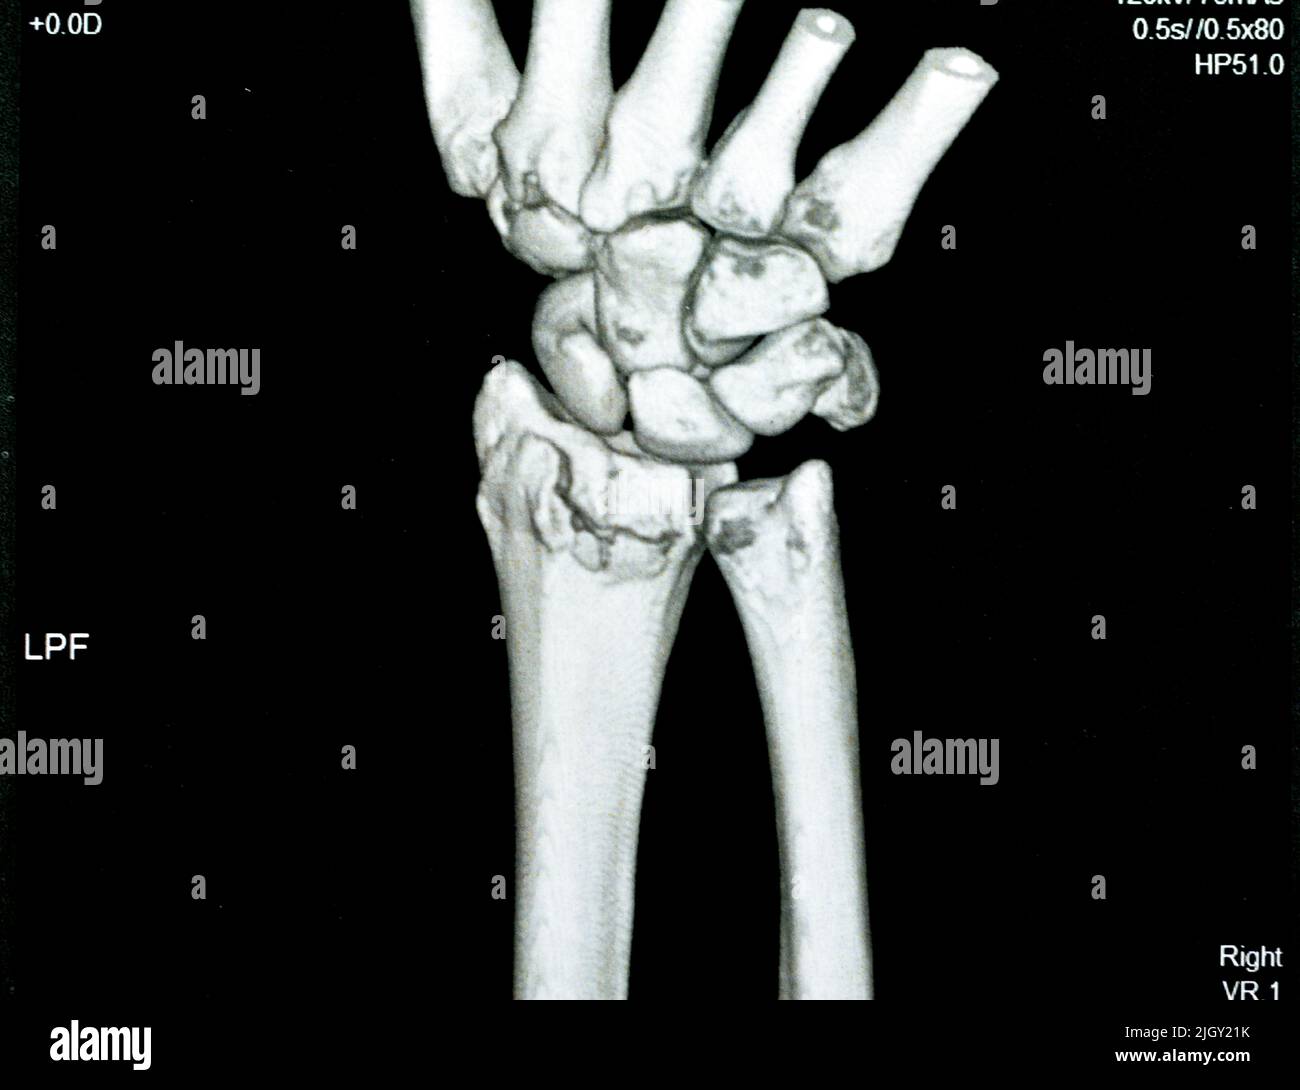

x ray of right hand and wrist

Posts: x ray of right hand and wrist